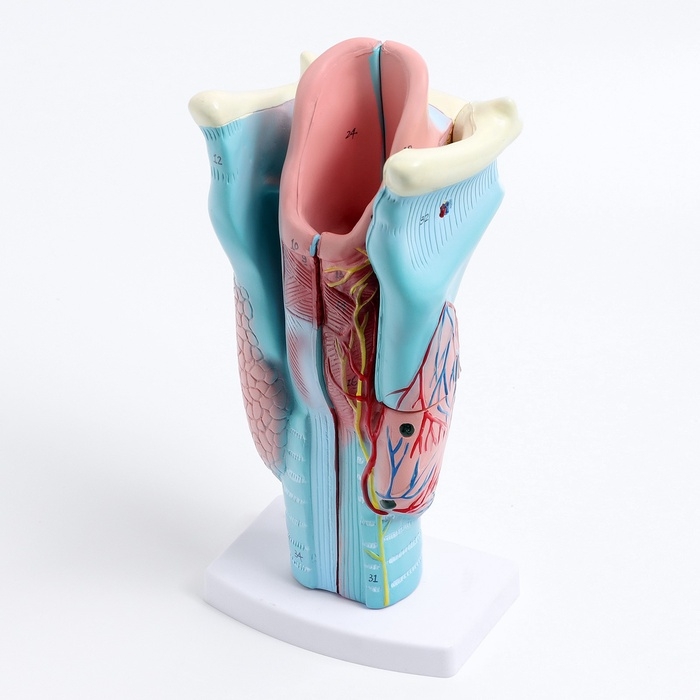

ЕКБ 167

No Brand, артикул: 7072352